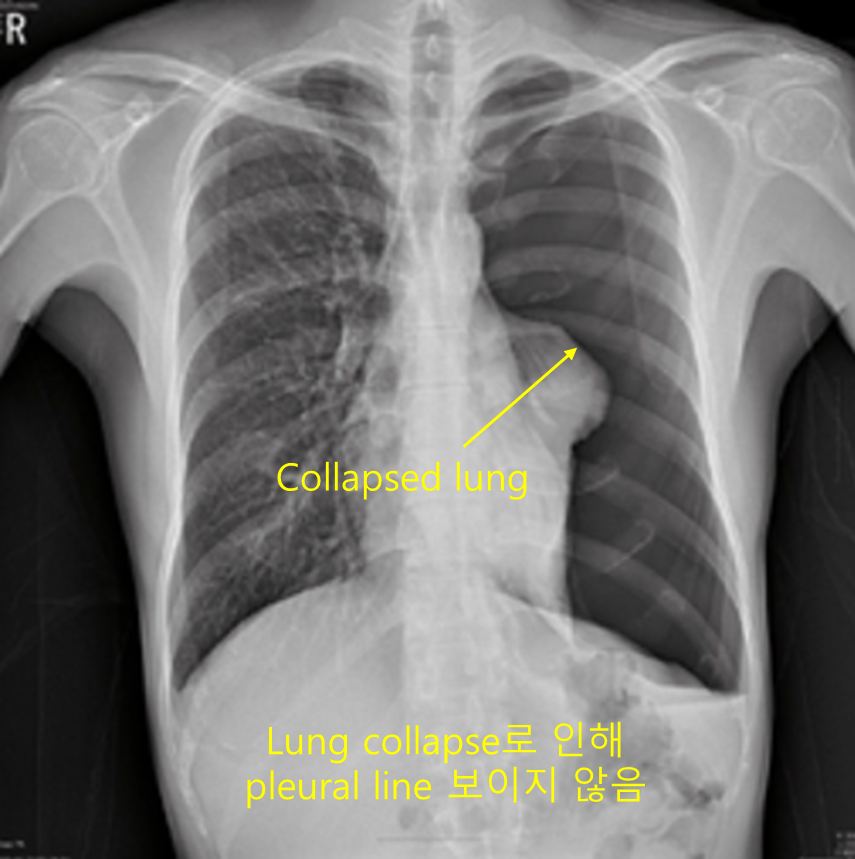

20세 남자가 2일 전부터 숨을 쉬기 힘들다며 응급실에 왔다. 혈압 110/70mmHg, 맥박 104회/분, 호흡 25회/분, 체온 37.1℃이다. 피부경유산소포화도는 95%이다. 왼쪽 가슴을 청진할 때 호흡음이 전혀 들리지 않는다. 가슴 X선 사진이다. 치료는?

Img | CXR: 좌측 폐혈관 음영 사라짐 |

병력과 CXR상 PSP 진단 하, 빈호흡이 있으며 Lt. lung total collapse가 있으므로 흉관 삽입을 시행한다.

• CXR에서 좌측 폐혈관 음영이 사라졌으므로 기흉으로 진단한다. 젊은 남성이며 특이 병력이 없는 것으로 보아 PSP로 진단한다.

• 현재 일반적인 기흉에서 관찰되는 pleural line이 보이지 않을 만큼 Lt. lung의 collapse가 심하며, RR > 24로 빈호흡이 있어 불안정하다고 판단되므로 흉관삽입이 필요하다.